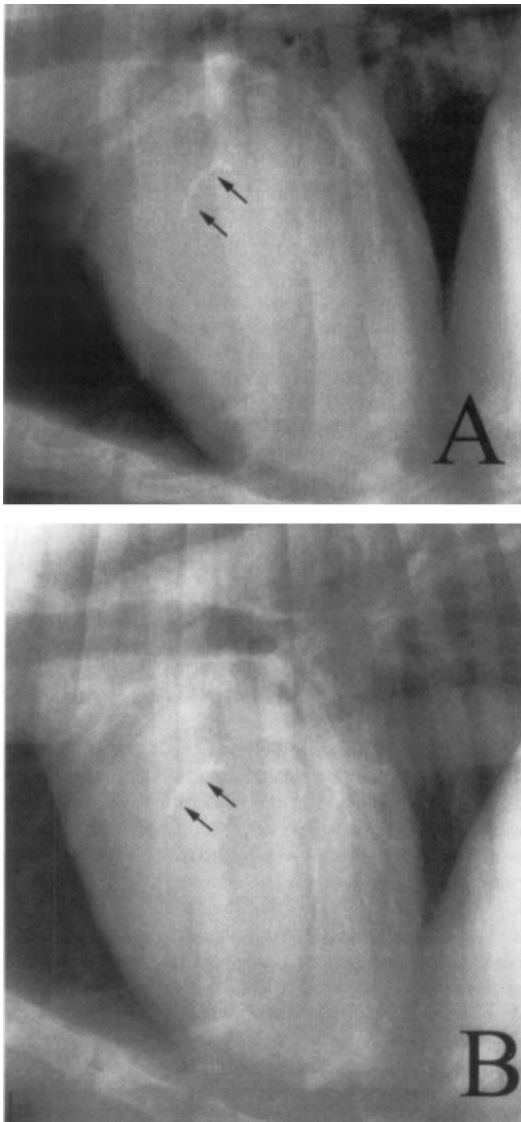

Murray et al: MRI and laminitis, **What were the consistent MRI findings of laminitis?**

Laminar disruption (See picture) Areas of laminar gas Laminar fluid Bone medullary fluid Other signs were increased size and number of vacular channels, alteration in the corium coronae, distal interphalangeal joint distension